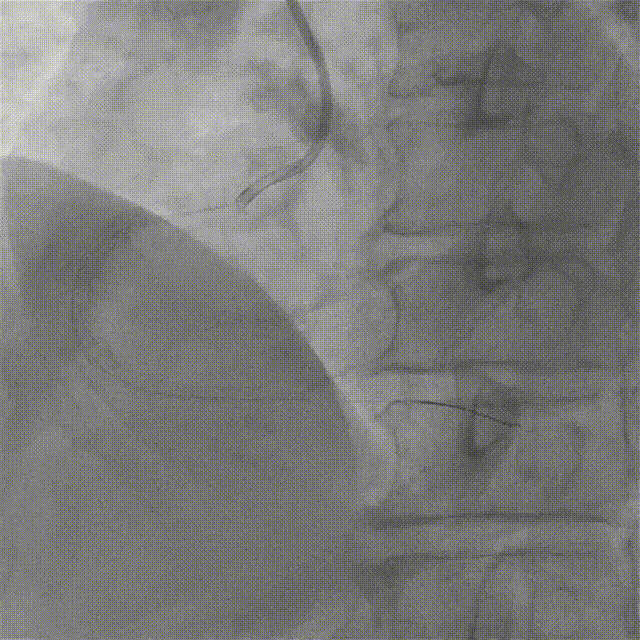

最终CAG和IVUS

术后造影及IVUS可见支架膨胀及贴壁良好,支架远近端未见夹层血肿。